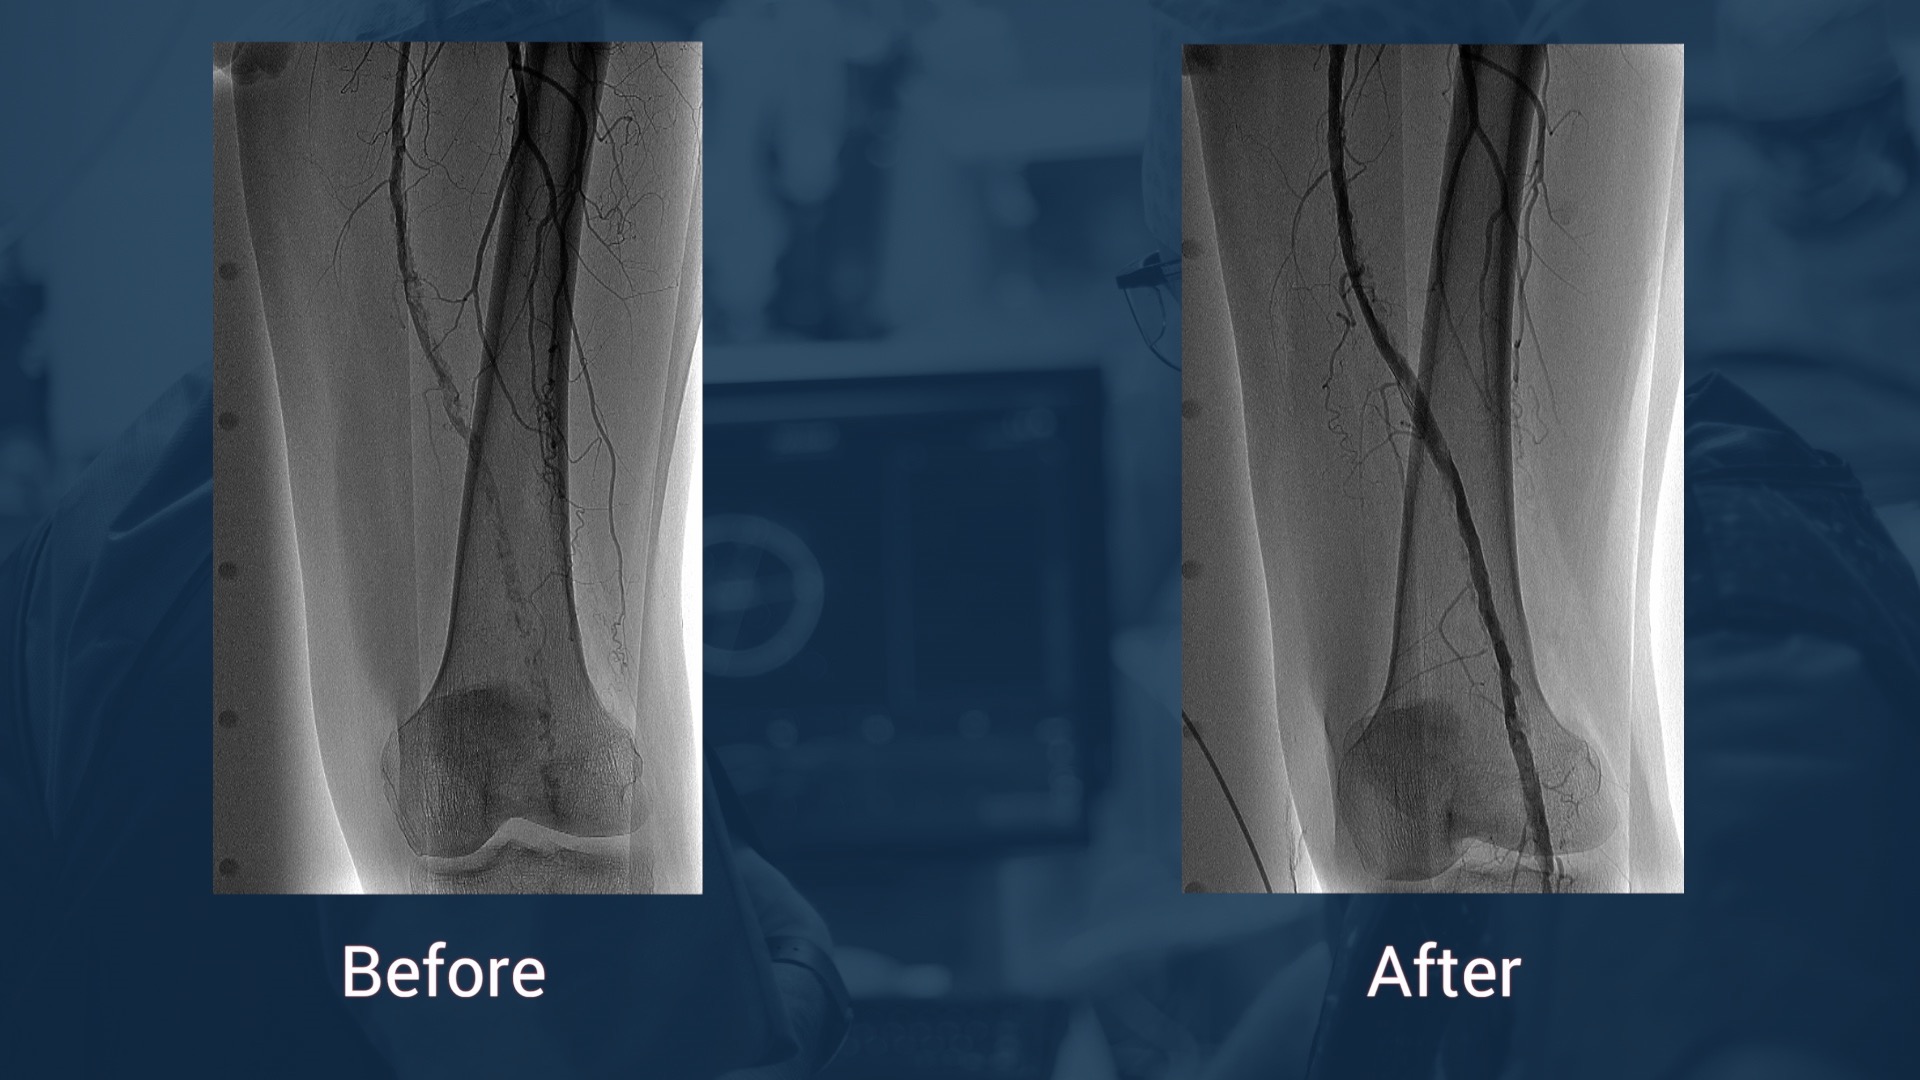

Live Case: Long Femoropopliteal lesion treated with scientifically proven drug eluting technologies